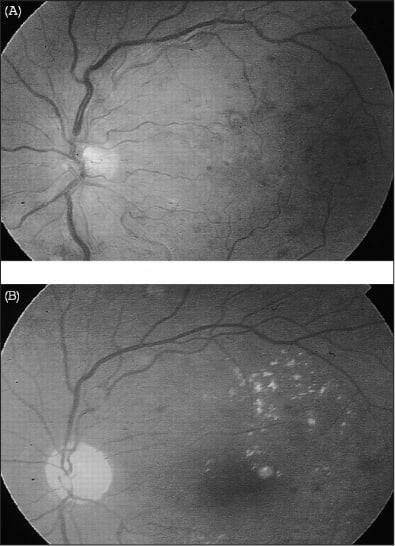

Susac's syndrome (Figure 1) is an uncommon disease presenting as a triad of microangiopathy of the brain, cochlea and retina, typically affecting young women between 20 and 40 years of age.8,9 Synonyms and mnemonics are variable: retinocochlearcerebral vasculopathy, RED-M syndrome (retinopathy, encephalopathy, deafness associated with microangiopathy) and SICRET syndrome (small infarcts of cochlear, retinal and encephalic tissues).10

Figure 1. Red-free photos and fluorescein angiograms of Susac's syndrome. Left eye: (A) red-free, (B) FA showing a white retinal edema due to the inferior temporal retinal arterial occlusion as well as multifocal wall hyperfluorescences. Right eye: (C, D) FA showing peripheral retinal arterial occlusion (arrow) and arterial wall hyperfluorescence distant from the occlusion site. IMAGE REPRINTED FROM RETINA: THE JOURNAL OF RETINAL AND VITREOUS DISEASES AND APPEARS WITH PERMISSION OF OPHTHALMIC COMMUNICATIONS SOCIETY, INC.

At presentation, central nervous system features occur in 80% of patients, cochlear involvement in 52% and retinal findings in 46%. Only 20% of patients present with the complete triad.11 Its prevalence is unknown, the female-to-male ratio is 3:1, and it has been reported in North America, Europe and Asia,12-14 as well as in children and adolescents.15 Because of the prominence of neurological and neuropsychiatric manifestations, patients with Susac's syndrome are often first evaluated by neurologists; the overwhelming neurologic symptoms and encephalopathy may initially obscure the diagnosis of cochlear and retinal involvement.16 The occurrence of deafness and eye involvement may lag behind the neurological findings by weeks or years.17 Finally, the syndrome may show a multiphasic pattern with a spontaneously relapsing-remitting course.18,19

Retinal findings include hallmark focal areas of narrowing and occlusions of small arterioles both in the posterior pole and periphery of the retina,8,9 giving the appearance of retinal arteritis or vasculitis.14 The findings are often seen initially in one eye but become bilateral over time if the disease is unrecognized and untreated.20 Even though an inflammatory pathogenesis has been posited for Susac's syndrome, the retinal vascular changes occur in eyes that are quiet or only minimally inflamed on slit-lamp examination. This is one point of differ entiation from Adamantiades-Behçet's disease or other forms of panuveitis.

Acutely, the focal occlusions can resemble branch retinal artery occlusions due to embolic or inflammatory processes such as giant cell arteritis. Careful retinal examination and systemic evaluation of the patient may be necessary to differentiate Susac's syndrome from cardiovascular disease or other forms of vasculitis affecting the eye and brain.21 Retinal ischemia is seen in the areas fed by the occluded arterioles, and remodeling of arterioles, microaneurysms and retinal hemorrhages characteristic of microangiopathy can be seen on retinal examination in more chronic cases.22 Retinal arterio-arteriolar collaterals may be seen in areas of ischemia resulting from the focal arteriolar occlusions, appearing as tortuous vessels crossing the area of ischemia.23 These collaterals are less common than their venous counterparts and thus indicate an arteriolar disease process such as Susac's syndrome. Additionally, a focal disruption of the endothelium associated with deposition of atheromatous, sometimes refractile, material called a Gass plaque has been described.11

Fluorescein angiography (FA) and, to a lesser extent, indocyanine green (ICG) angiography are essential in diagnosing Susac's syndrome in the eye.20 The pathognomonic lesion in Susac's syndrome is multifocal and has segmental areas of arteriolar narrowing with leakage of dye from the involved segments. If these leakages occur in multiple portions of a single arteriole, they may resemble boxcars. The occurrence of focal arteriolar occlusions in different retinal vessels, in different quadrants, and in one or both eyes points to this disease; indications of multiple emboli or thrombophlebitis would implicate another disease process. The occlusions do not necessarily occur at the branches of the arterioles,24 in contrast to emboli or thrombi.

The presence of scattered, geographically diverse areas of retinal ischemia with microvascular changes and arterio-arteriolar collaterals could also appear in an FA, suggesting a more chronic process. FA also shows that retinal veins are not involved in the occlusive vasculopathy, although changes in venules may occur in areas of chronic retinal ischemia.22 In contrast to the other entities discussed in these articles, ICG angiography shows no evidence of significant choroidal involvement in this retinal vasculopathy.